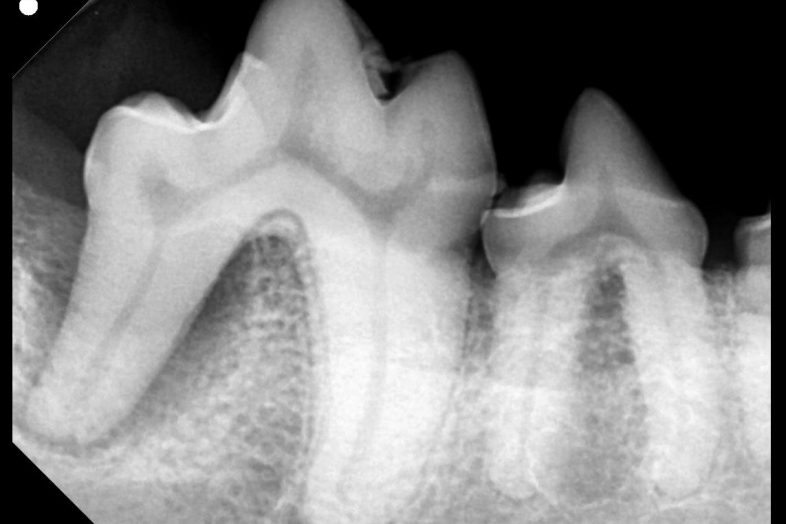

- Radiología dental

El veterinario comienza su revisión con un examen de la boca de la mascota. Para evaluar el estado de la mandíbula y de las raíces de los dientes tal vez necesite realizar unas radiografías. Las limpiezas dentales se realizan bajo anestesia general para garantizar un tratamiento más completo.

La anestesia permite realizar los tratamientos dentales con menos estrés y dolor. Además, permite realizar una mejor limpieza porque el paciente no se mueve y no corre riesgo de lesionarse con el equipo dental. Si hay necesidad de hacer radiografías, el paciente tiene que estar inmóvil para obtener imágenes nítidas y esto es difícil de conseguir a menos que esté bajo los efectos de la sedación.

La enfermedad periodontal comienza con el endurecimiento de la placa bacteriana que se convierte en sarro. El sarro por encima de la encía a menudo puede verse y eliminarse fácilmente, pero la placa y el sarro por debajo de la encía son perjudiciales, favorecen la infección y perjudican la mandíbula y los tejidos que la conectan con el diente. La enfermedad periodontal se clasifica en una escala de 0 (normal) a 4 (grave).

El tratamiento para esta afección es una limpieza dental completa; es posible que se necesiten radiografías para determinar la gravedad de las lesiones y un tratamiento médico que elimine la infección y la inflamación. Nuestros veterinarios te aconsejarán qué hacer, basándose en la salud general de la mascota y la salud de sus dientes.